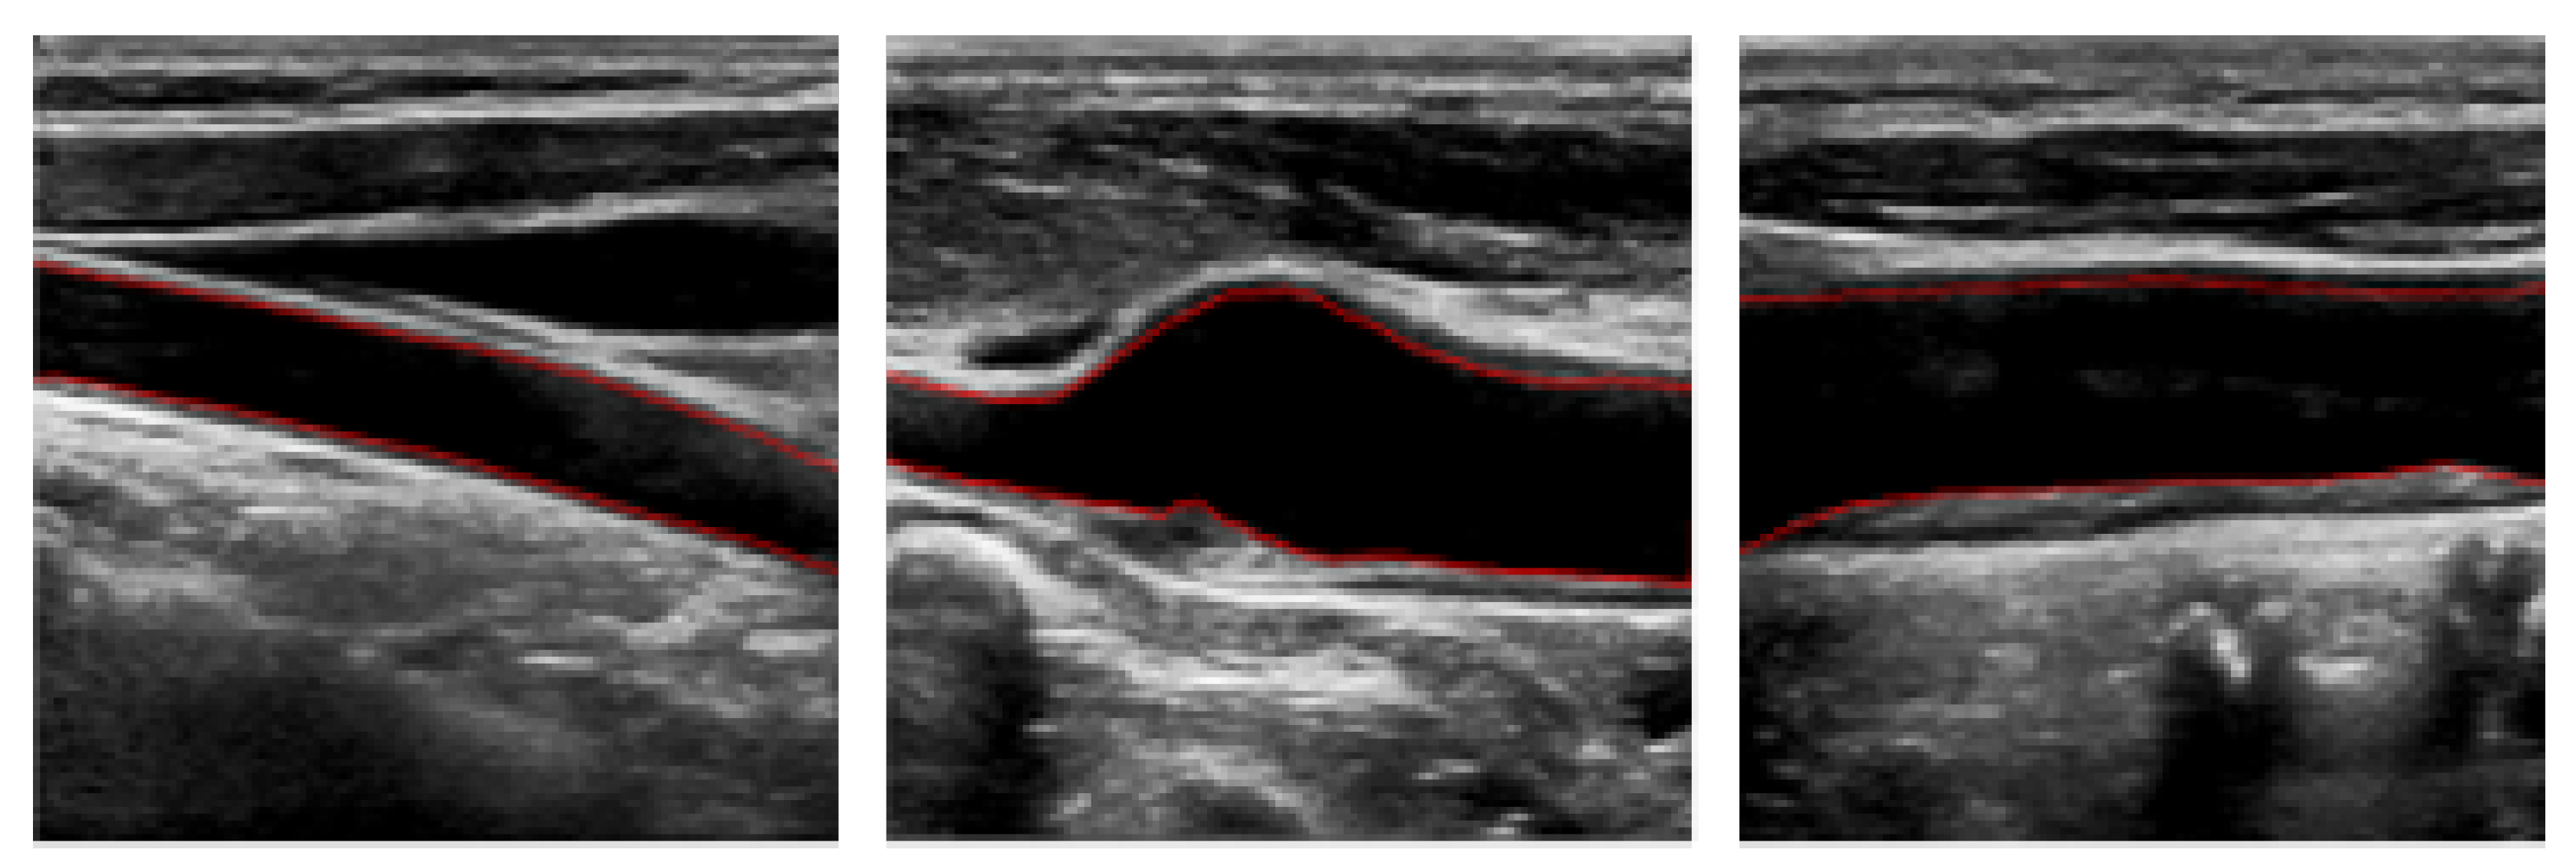

3.4. Experimental Results